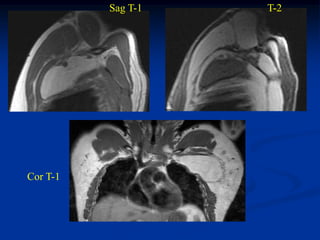

Case #1196.2 Ossifying Lipoma Cor T-1 Axial T-2 53 yr male with painless mass in knee for 3 yrs